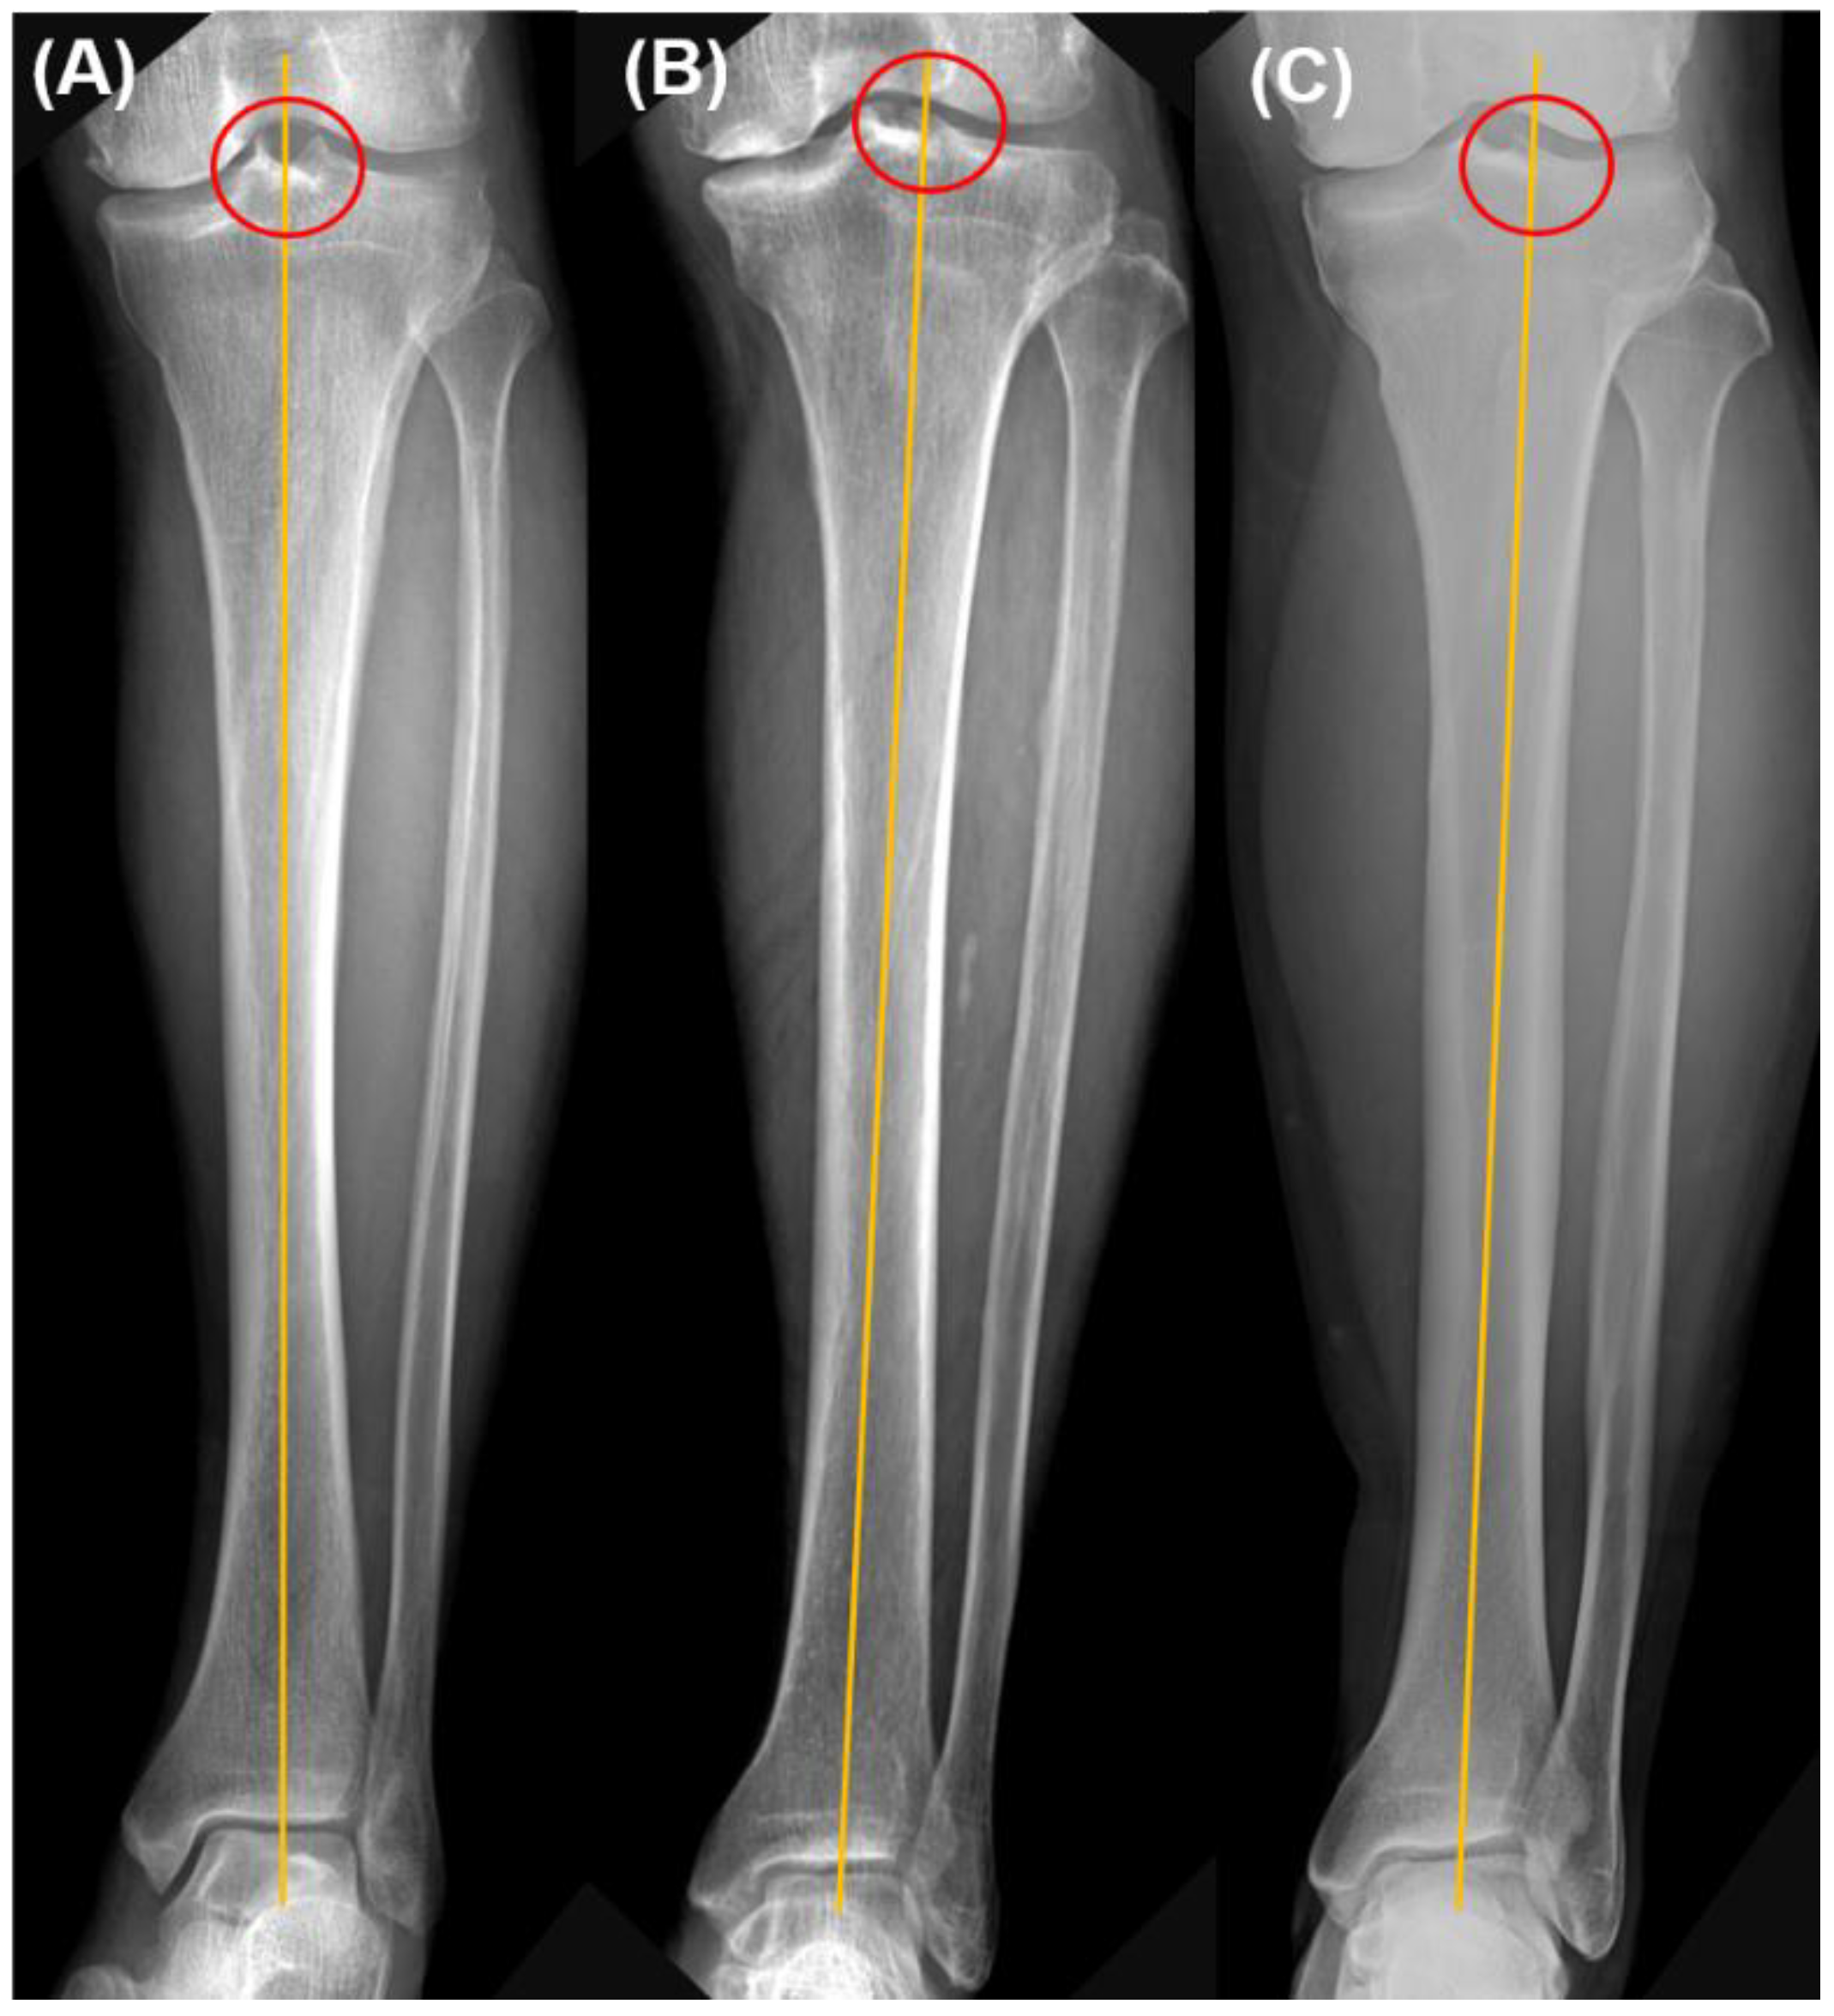

| Proximal tibial reference point | |

| Center | 157 (71.4%) |

| In-between | 24 (10.9%) |

| Lateral tibial spine | 39 (17.7%) |